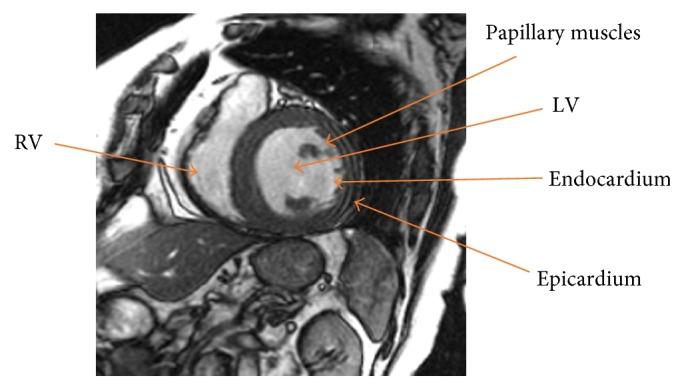

Segmentation of left and right ventricles plays a crucial role in quantitatively analyzing the global and regional information in the cardiac magnetic resonance imaging (MRI). In MRI, the intensity inhomogeneity and weak or blurred object boundaries are the problems, which makes it difficult for the intensity-based segmentation methods to properly delineate the regions of interests (ROI). In this paper, a hybrid signed pressure force function (SPF) is proposed, which yields both local and global image fitted differences in an additive fashion. A characteristic term is also introduced in the SPF function to restrict the contour within the ROI. The overlapping dice index and Hausdorff-Distance metrics have been used over cardiac datasets for quantitative validation. Using 2009 LV MICCAI validation dataset, the proposed method yields DSC values of 0.95 and 0.97 for endocardial and epicardial contours, respectively. Using 2012 RV MICCAI dataset, for the endocardial region, the proposed method yields DSC values of 0.97 and 0.90 and HD values of 8.51 and 7.67 for ED and ES, respectively. For the epicardial region, it yields DSC values of 0.92 and 0.91 and HD values of 6.47 and 9.34 for ED and ES, respectively. Results show its robustness in the segmentation application of the cardiac MRI.

左心室和右心室的分割在定量分析心脏磁共振成像(MRI)中的全局和局部信息方面起着至关重要的作用。在MRI中,强度不均匀性以及目标边界模糊或微弱是存在的问题,这使得基于强度的分割方法难以准确勾勒出感兴趣区域(ROI)。本文提出了一种混合符号压力力函数(SPF),它以相加的方式产生局部和全局图像拟合差异。在SPF函数中还引入了一个特征项,以将轮廓限制在ROI内。重叠骰子指数和豪斯多夫距离度量已用于心脏数据集进行定量验证。使用2009年左心室MICCAI验证数据集,所提出的方法对于心内膜和心外膜轮廓分别产生0.95和0.97的DSC值。使用2012年右心室MICCAI数据集,对于心内膜区域,所提出的方法对于舒张末期(ED)和收缩末期(ES)分别产生0.97和0.90的DSC值以及8.51和7.67的HD值。对于心外膜区域,对于ED和ES分别产生0.92和0.91的DSC值以及6.47和9.34的HD值。结果表明了其在心脏MRI分割应用中的鲁棒性。